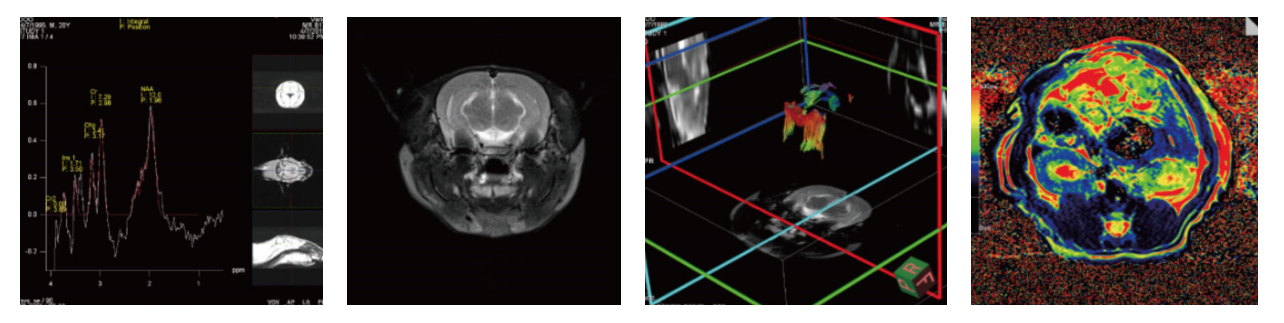

图

2 结果展示

四、案例展示

(1)脑部核磁检测应用

2)结肠癌核磁检测应拥